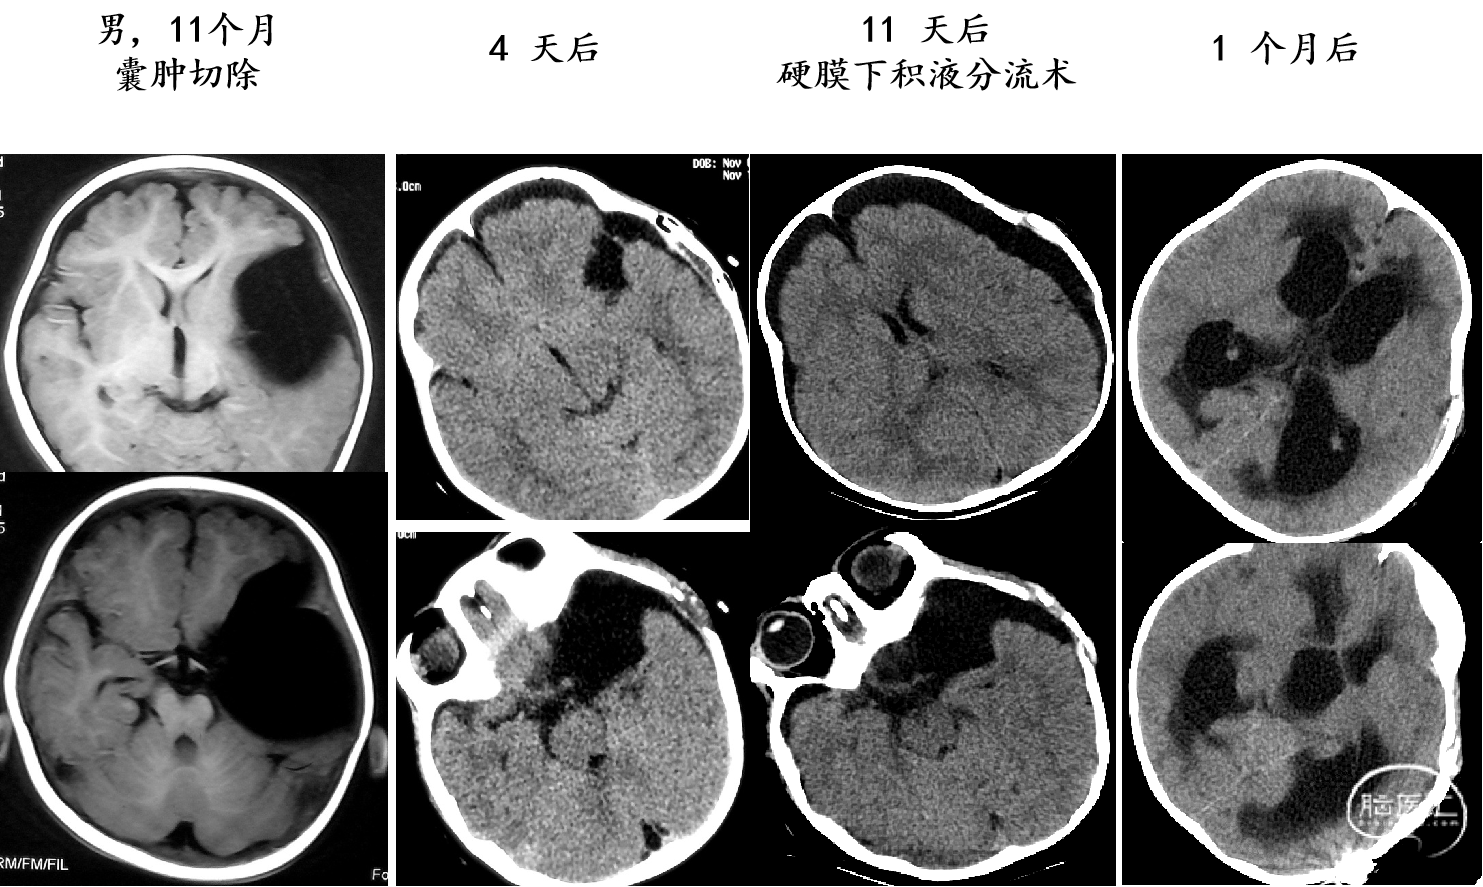

2岁以下囊肿切除/造瘘术后出现积液(Hg)/积水(Hc)

囊肿切除术后出现积液/积水

婴儿巨大囊肿:我们建议囊肿腹腔分流术(可调压分流管)需密切随访分流管依赖综合征可能